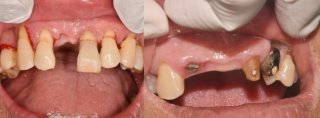

임플란트 시술의 주요 장점

1. 자연 치아와 유사한 저작 기능으로 음식 섭취가 편리함

2. 외관상 자연스러워 자신감 회복 가능

3. 발음 교정 효과로 원활한 의사소통

4. 주변 치아를 손상시키지 않고 독립적으로 식립 가능

5. 턱관절 균형 유지로 구강 건강 보호